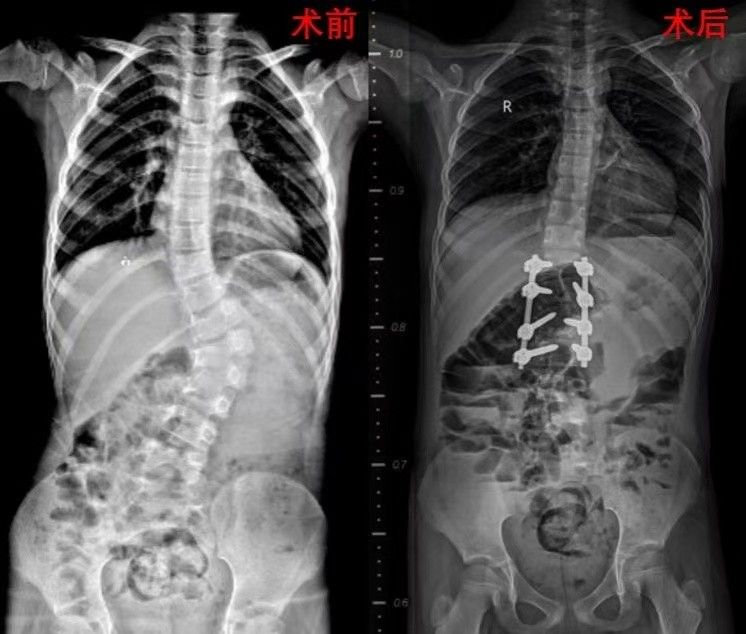

近日脊柱骨肿瘤病区收治了一位7岁的脊柱侧凸患儿,患儿近4年腰背部隆起加重,久坐酸困,X片提示胸腰段侧弯呈S型改变,脊柱侧凸的cobb角度达58°,躯干伴随失衡。在王栋主任主刀和张廷副主任医师、李京主治医师的密切配合下择期实施了手术。